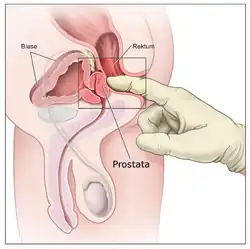

Da Beschwerden beim Wasserlassen und Blasenentleerungsstörungen viele Ursachen haben können, ist es die Aufgabe der Diagnostik zu klären, ob eine BPH ursächlich ist.[19] Eine Vergrößerung der Prostata wird bei der rektal-digitalen Untersuchung ertastet und kann, sofern notwendig, mittels rektaler Ultraschalluntersuchung ausgemessen werden. Beschwerden sind mittels urodynamischer Untersuchung objektivierbar, wobei ein erniedrigtes Harnstrahlvolumen und eine relevante Restharnbildung nicht zwingend auf ein BPH schließen lassen. Eine Schwäche des Blasenmuskels (Detrusorschwäche) würde die gleichen Symptome verursachen.[17] Ein Aufstau der Harnwege kann, sofern die Notwendigkeit dazu besteht, mittels Ultraschall oder Urogramm dargestellt werden. Ziel der Untersuchung ist es herauszufinden, inwieweit die Beschwerden des Patienten mit der BPH in Zusammenhang stehen. Des Weiteren wird abgeklärt, ob ein Behandlungsbedarf besteht, und wenn ja, welche Therapieform die geeignetste ist. Kommen zudem dabei von der BPH unabhängige, auffällige Befunde zutage (Screening), wie beispielsweise ein auffälliger Tastbefund, ein PSA-Wert über 4 oder unklare, sonographische Inhomogenität der Drüse, sind weiterführende Untersuchungen zum Ausschluss eines Prostatakrebses angezeigt.

Die körperliche Untersuchung besteht insbesondere aus der rektal-digitalen Tastuntersuchung, bei der nicht nur die Prostata beurteilt wird, sondern auch der Analsphinktertonus (Spannung des Schließmuskels des Afters) und der Bulbo-cavernosus-Reflex. Ergänzend wird ein orientierender motorischer und sensorischer Status des Dammes, der Genitale und der unteren Extremitäten erhoben.